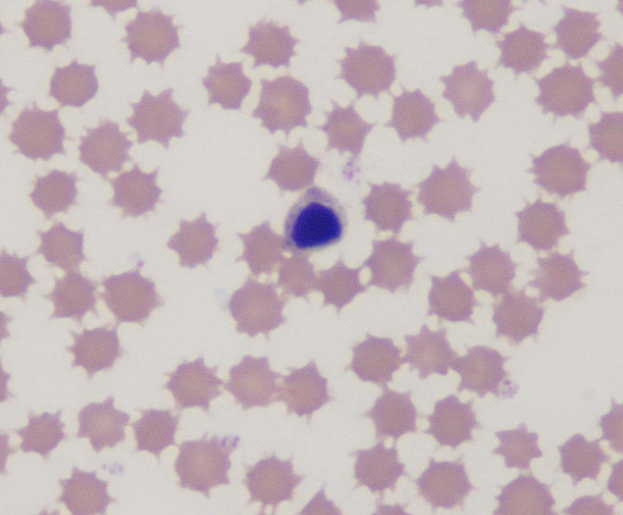

wbc

apoptotic wbc

horse